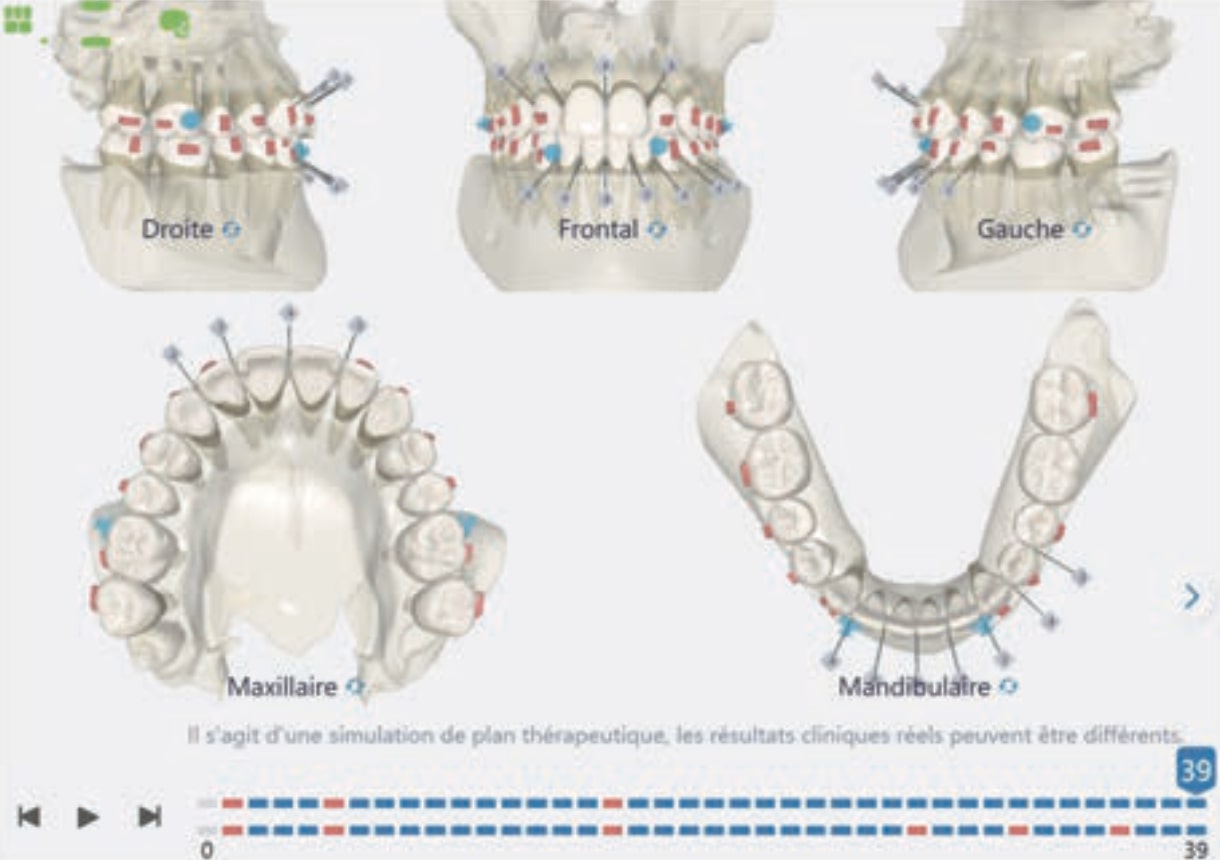

Number of aligners: 39

- Distalization of the Third and Fourth Quadrants: Move the teeth distally in these quadrants to achieve a Class I relationship using the A8 protocol, improving the patient’s dental alignment and occlusion.

- Solve the Crossbite of Tooth 33: Correct the position of tooth 33 to eliminate the crossbite, contributing to a more balanced occlusion.

- Intrusion of the Lower Anterior Teeth: Adjust the vertical position of the lower anterior teeth to level the curve of Spee, improving the harmony of the occlusion.

- Improve the Root Position of Teeth 33 and 43: Optimize the position of the roots of teeth 33 and 43 in relation to the cortical bone to ensure adequate bone support and long-term stability.

Treatment setup